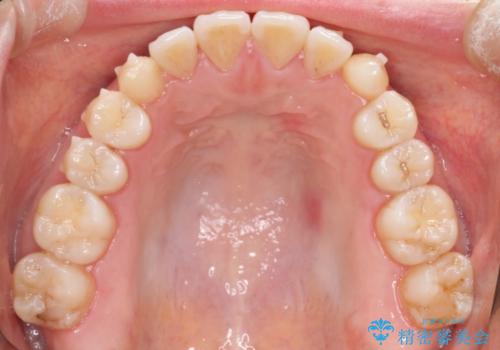

初診時の歯並びの状態としては、上下ともに前歯部に限局した軽度ののがたつき(叢生)がある状態でした。

主に歯列弓の拡大とディスキング(歯と歯の間に隙間を作る処置)を行い叢生を改善しました。